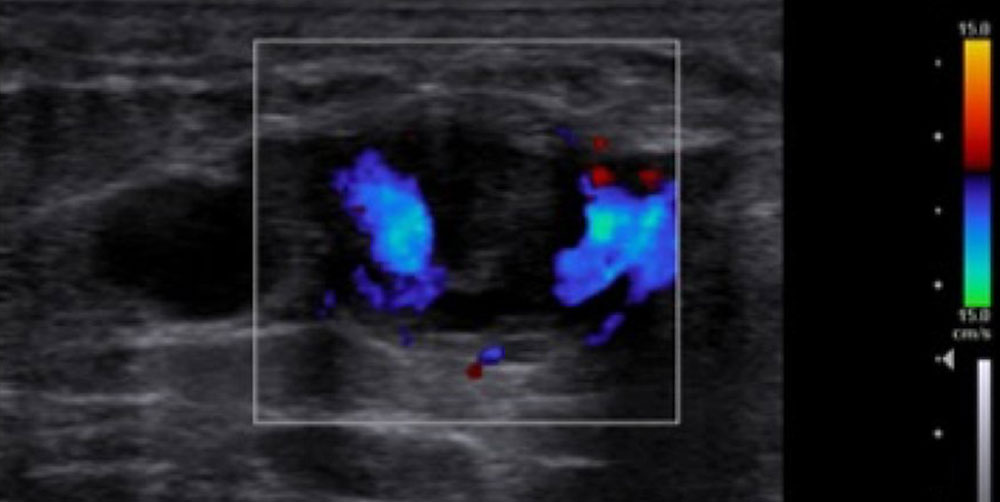

The most important imaging to detect or exclude phlebothrombosis is sonography. The affected vein section shows the thrombus contained in the vessel lumen, which cannot be compressed by compressing the vein with the transducer. Depending on age, this vascular thrombus tends to have a relatively low echogenicity initially in acute cases. The vein diameter is significantly increased by the intraluminal thrombus in the acute phase. In color-coded duplex sonography (CCDS), no color signal is found in the vein owing to the lack of blood flow, even at very low PRF settings (low pulse repetition frequency PRF = high detection sensitivity for flowing blood). With increasing thrombus age, the thrombus shrinks in size and becomes increasingly echogenic. In the further course, at least partial recanalization of the thrombosed vein occurs in favorable cases. Often beginning at the vein wall, blood (echo-free on ultrasound) again flows through the vessel surrounding the thrombus.